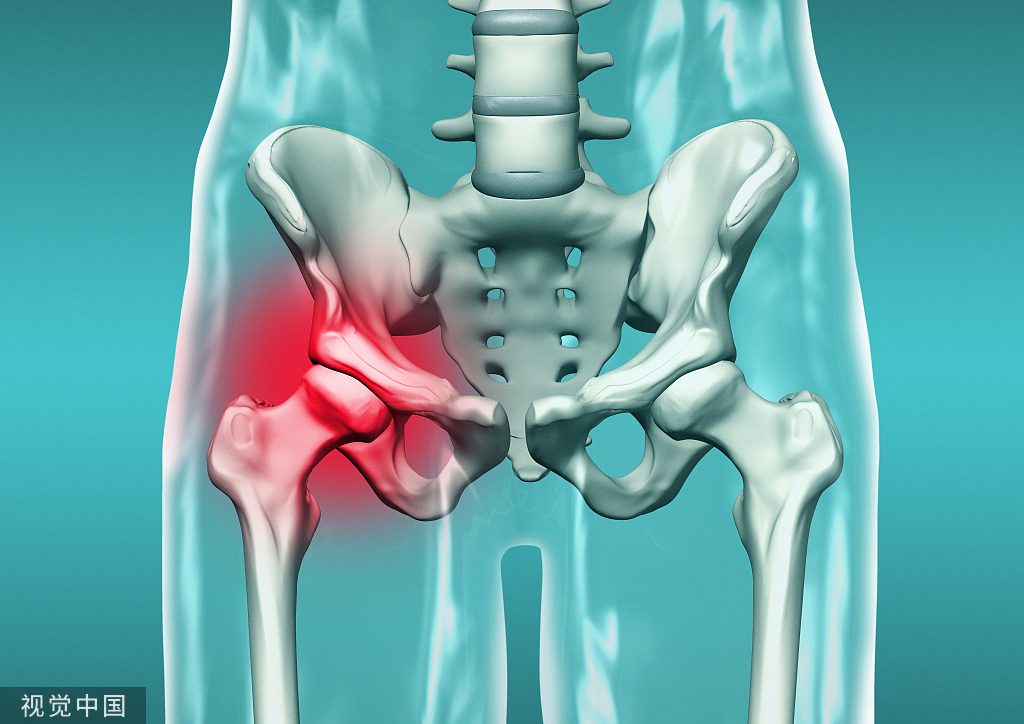

面对髋关节脱位,你的处理方法对吗?

髋关节脱位多为高暴力损伤,暴力间接作用于髋关节导致关节脱位,且髋关节脱位的方向同受伤时的体位有很大相关性。